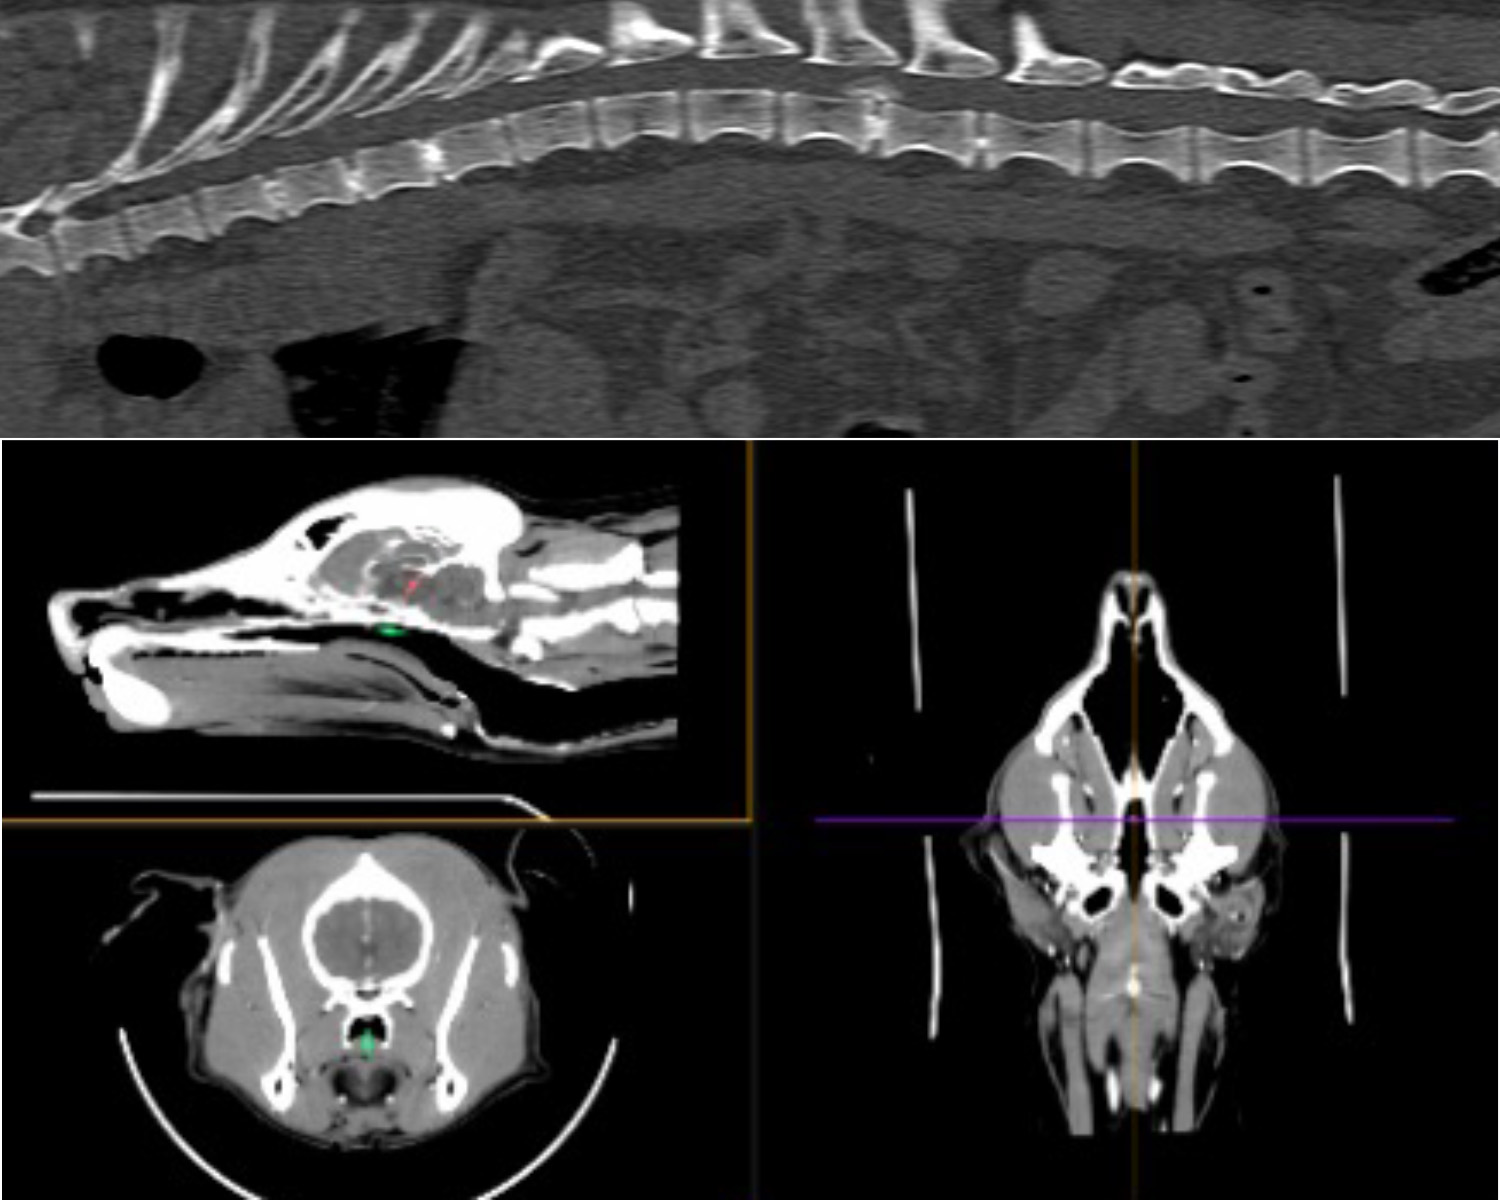

Bay Vets Referrals (Lancaster and Milnthorpe branches) provides expertise in orthopaedic and soft tissue surgical cases. Bay Vets Director Colin Houston BVM&S CertSAS MRCVS leads our referral team, offering his expertise to all our registered clients as well as accepting referrals from other veterinary surgeons in the North-West.

Bay Vets referrals is based from our Lancaster Practice and provides expertise for the more complex orthopaedic and soft tissue surgical cases . It is lead by one of the directors of Bay Vets, Colin Houston BVM&S CertSAS MRCVS. Colin offers his expertise to all of our registered clients as well as accepting referrals from other veterinary surgeons in the north west. Should your pet be unfortunate enough to need a complex operation, this can usually be done without the need for them to travel to another Veterinary specialist, who are often based miles away.